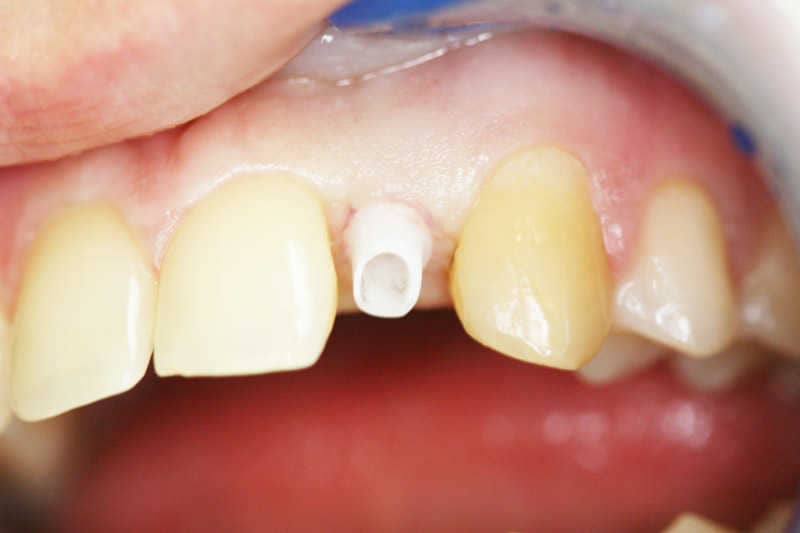

A cirkonfelépítmény látható az implantátumba rögzítve